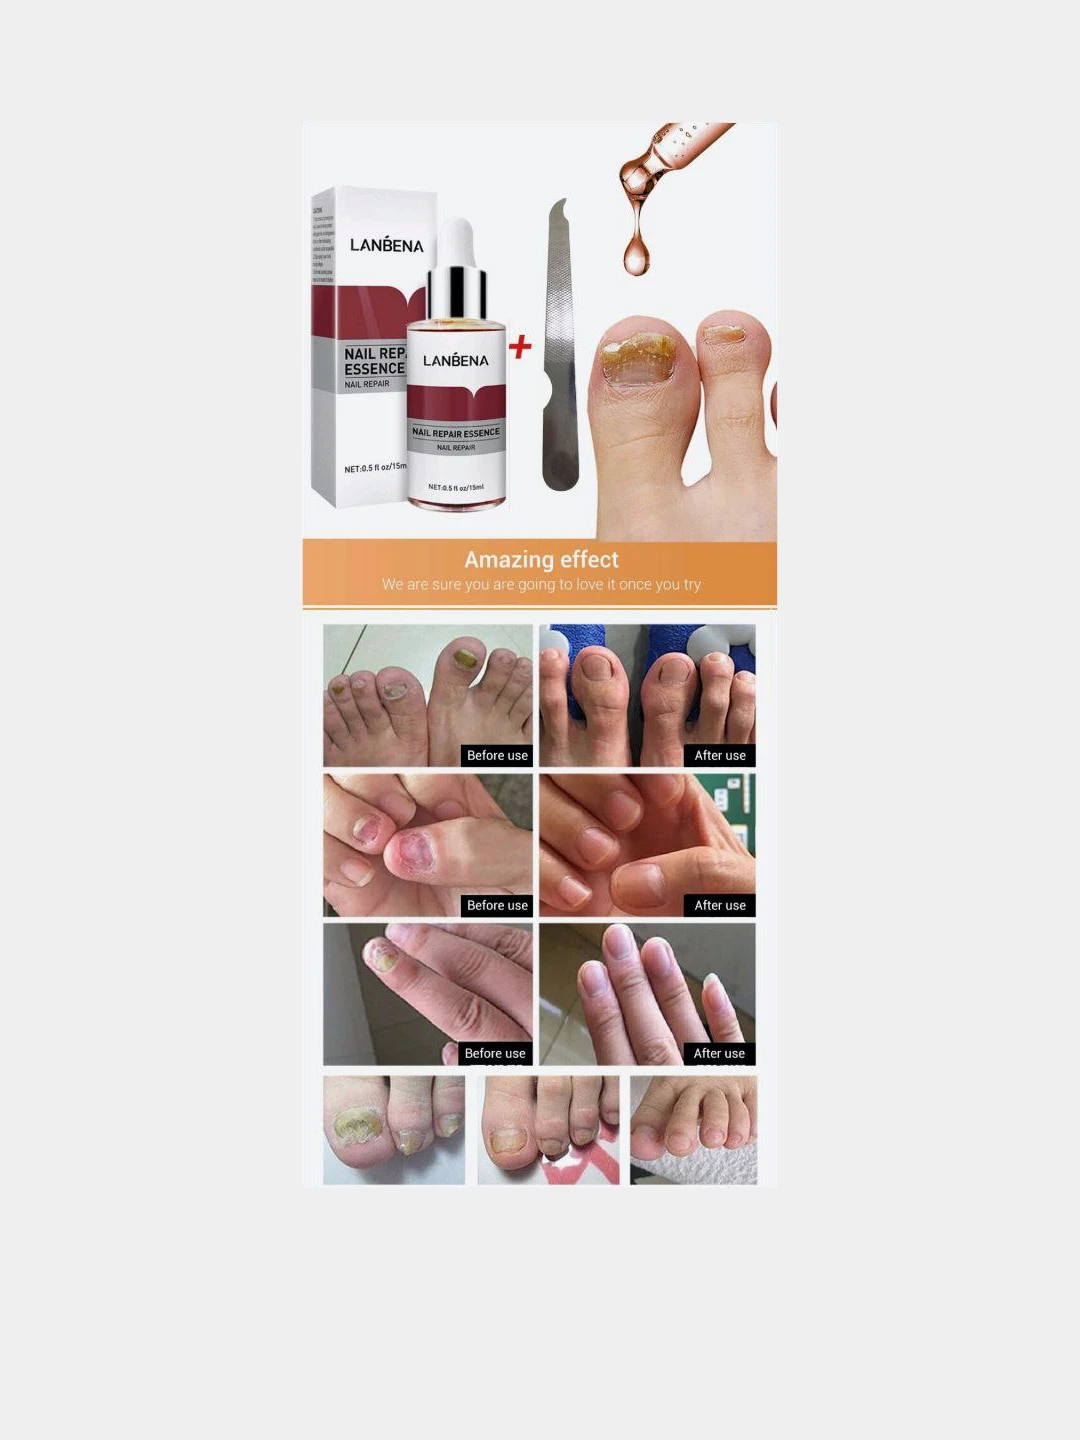

Раздел: Необычные решения